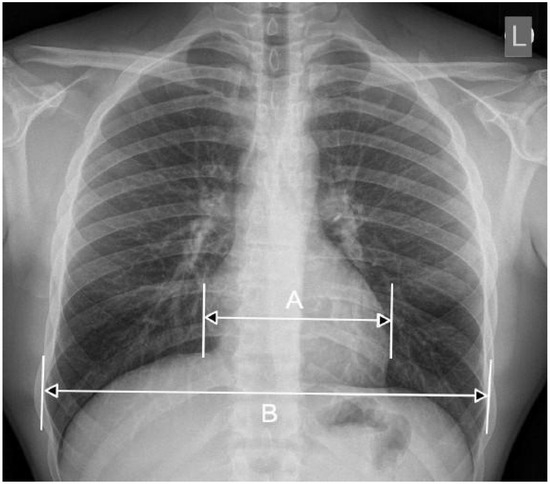

In parallel, data augmentation techniques were applied during training to artificially expand the dataset and introduce greater variability. Augmentations included random rotation, zoom, and horizontal flipping, simulating real-world variations in imaging conditions. Additionally, CLAHE was applied to enhance local contrast, improving feature visibility in low-intensity regions—common in medical images. These preprocessing steps collectively aimed to enhance model generalization and reduce bias toward specific imaging conditions.

3.2.2. Clinically Aware Data Augmentation

Data augmentation was carefully designed to increase dataset variability while preserving the thoracic anatomical structures critical for cardiomegaly assessment.

Horizontal flipping was applied with a 50% probability, as frontal chest radiographs maintain diagnostic validity regardless of left–right symmetry in most cardiomegaly cases [29].

Rotation was constrained to a small range of ±5 degrees, as larger rotations could deform key structures such as the heart silhouette or mediastinum, which are essential for accurate diagnosis.

Zoom augmentation was applied within a narrow range of 95% to 105%, simulating realistic changes in radiographic magnification during image acquisition while avoiding the disproportionate enlargement of the heart or lungs.

Translation was limited to ≤5% of the image width or height (i.e., maximum shifts of approximately ±10 to 12 pixels) along the x- and y-axes to simulate minor variations in patient positioning without displacing core anatomical features.

Additionally, combinations of flipping and translation were used selectively to further enhance spatial diversity without compromising clinical interpretability [29].

3.2.3. Contrast Enhancement with CLAHE

To improve the visibility of thoracic anatomical landmarks in low-contrast images, Contrast-Limited Adaptive Histogram Equalization (CLAHE) was applied. The enhancement process was conducted on the luminance channel after converting the image from RGB to the LAB color space. CLAHE was implemented using a clip limit of 2.0 and a tile grid size of 8 × 8, parameters optimized to enhance local contrast while preventing the over-amplification of noise. This method improved contrast along subtle cardiac contours and lung borders, thereby aiding the model in detecting cardiomegaly-related features. Furthermore, to ensure consistent preprocessing across all datasets, a binary K-Means clustering algorithm was used to detect white-background images, which were then inverted to match the standard dark-background format used in CXR interpretation [29].

Figure 7 shows examples of images to which data augmentation techniques have been applied. Table 4 provides a detailed explanation of the types of data augmentation, their settings, and their clinical purposes.

Figure 7.

Data augmentation example.